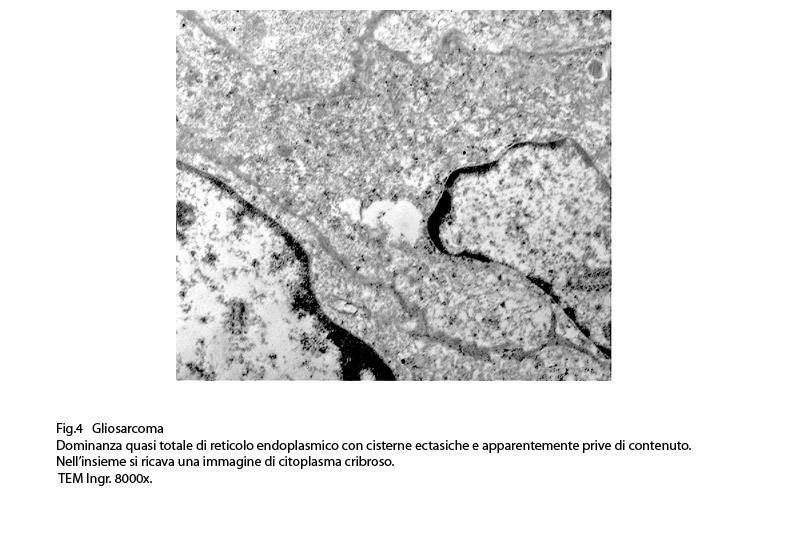

Fig.4

RETICOLO ENDOPLASMICO

Anche il reticolo endoplasmico mostra segni ultrastrutturali di stress sia in associazione all’ergastoplasma sia in situazioni univoche.

Infatti,si repertano cellule di gliosarcoma con l’ ampio citoplasma occupato quasi interamente da queste formazioni; esse sono molto numerose, si trovano tra loro adese e mostrano le loro cisterne ectasiche o micro cistiche, creando così in una visione panoramica una immagine di aspetto cribroso .Lo spazio interno alle cisterne è apparentemente privo di contenuto, o, più raramente, è occupato da materiale amorfo, debolmente elettropaco.